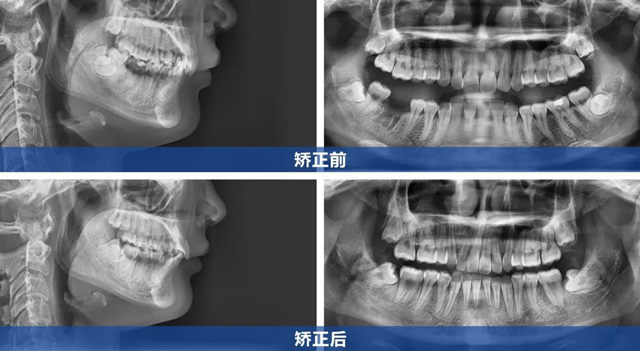

顧客上前牙內(nèi)扣且咬合較深,屬于內(nèi)傾性深覆合(即上牙覆蓋下牙的范圍較大,且上前牙向內(nèi)傾斜,幾乎完全覆蓋住下牙)。矯正內(nèi)傾牙時(shí)需精準(zhǔn)控制前牙外移角度,既要解除深覆合,又要避免上唇過度前凸影響面型。

同時(shí),顧客就診前缺右下第一磨牙,左下第一磨牙嚴(yán)重齲壞需要拔除,下頜兩個(gè)磨牙空缺跨度較大,關(guān)閉間隙過程中需控制下后牙移動(dòng)的角度,避免出現(xiàn)鄰牙傾斜。

在與顧客充分溝通后,根據(jù)顧客訴求及CBCT檢查結(jié)果,我們制定了拔牙矯治的方案:

1、上頜對(duì)稱性拔除兩顆第一前磨牙,為前牙調(diào)整創(chuàng)造空間

2、拔除左下齲壞嚴(yán)重的第一磨牙

3、采用金屬托槽精細(xì)調(diào)整牙齒移動(dòng)軌跡,排齊牙齒,解除內(nèi)傾性深覆合

4、利用下后牙向前移動(dòng)來關(guān)閉間隙

5、收完間隙后再整體進(jìn)行精細(xì)調(diào)整

楊女士成功告別牙套后,曾經(jīng)內(nèi)扣的上前牙變得平直,面部輪廓更顯自然流暢,如今的她,笑容自信綻放,舉手投足間盡顯開朗。